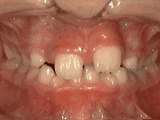

Fase I

Los padres de este paciente de 8 años estaban muy preocupados con la apariencia y la salud de los dientes permanentes que le estaban erupcionando al menor. Es por esta razón que decidieron llevarlo con el ortodoncista. Los dientes frontales inferiores estaban apiñados y hacían contacto con el paladar, y los dientes frontales superiores estaban muy desplazados de su posición normal. Después de 20 meses de tratamiento de fase I con un expansor y frenos parciales, la apariencia y función dental del paciente mejoraron considerablemente.